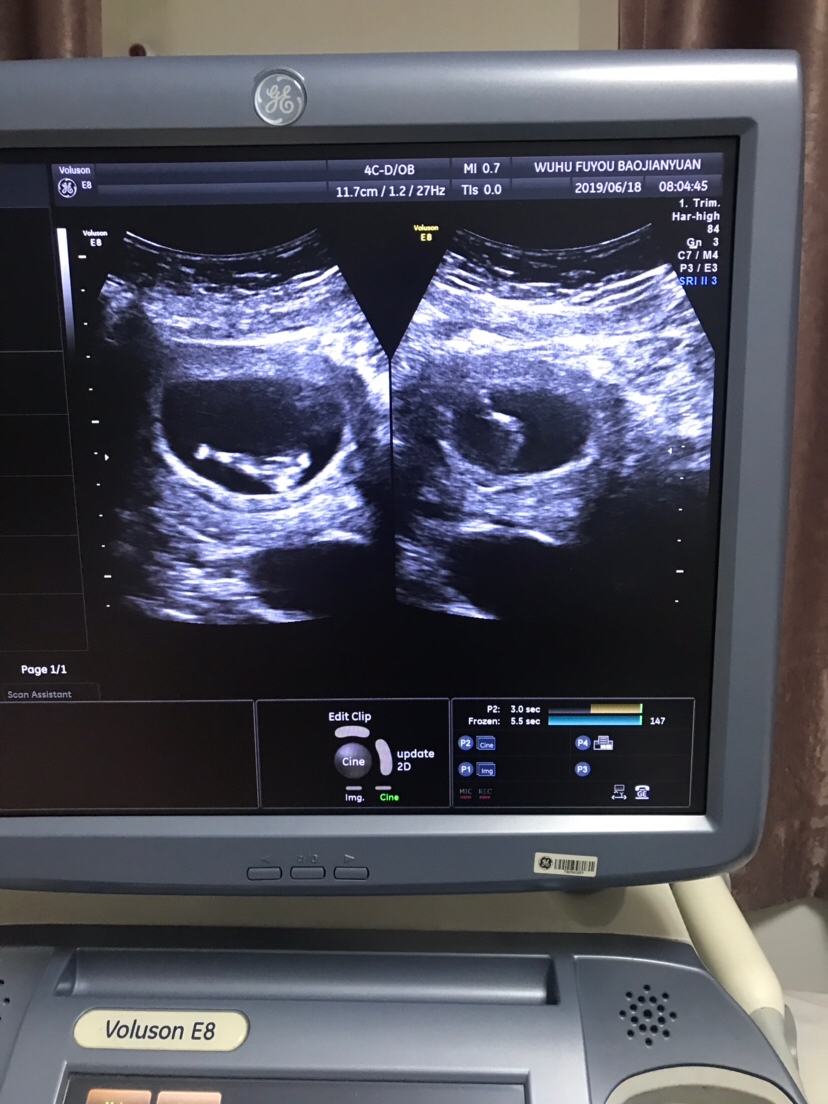

可乐双胞胎兄弟

2018-06-01

2736 人回复